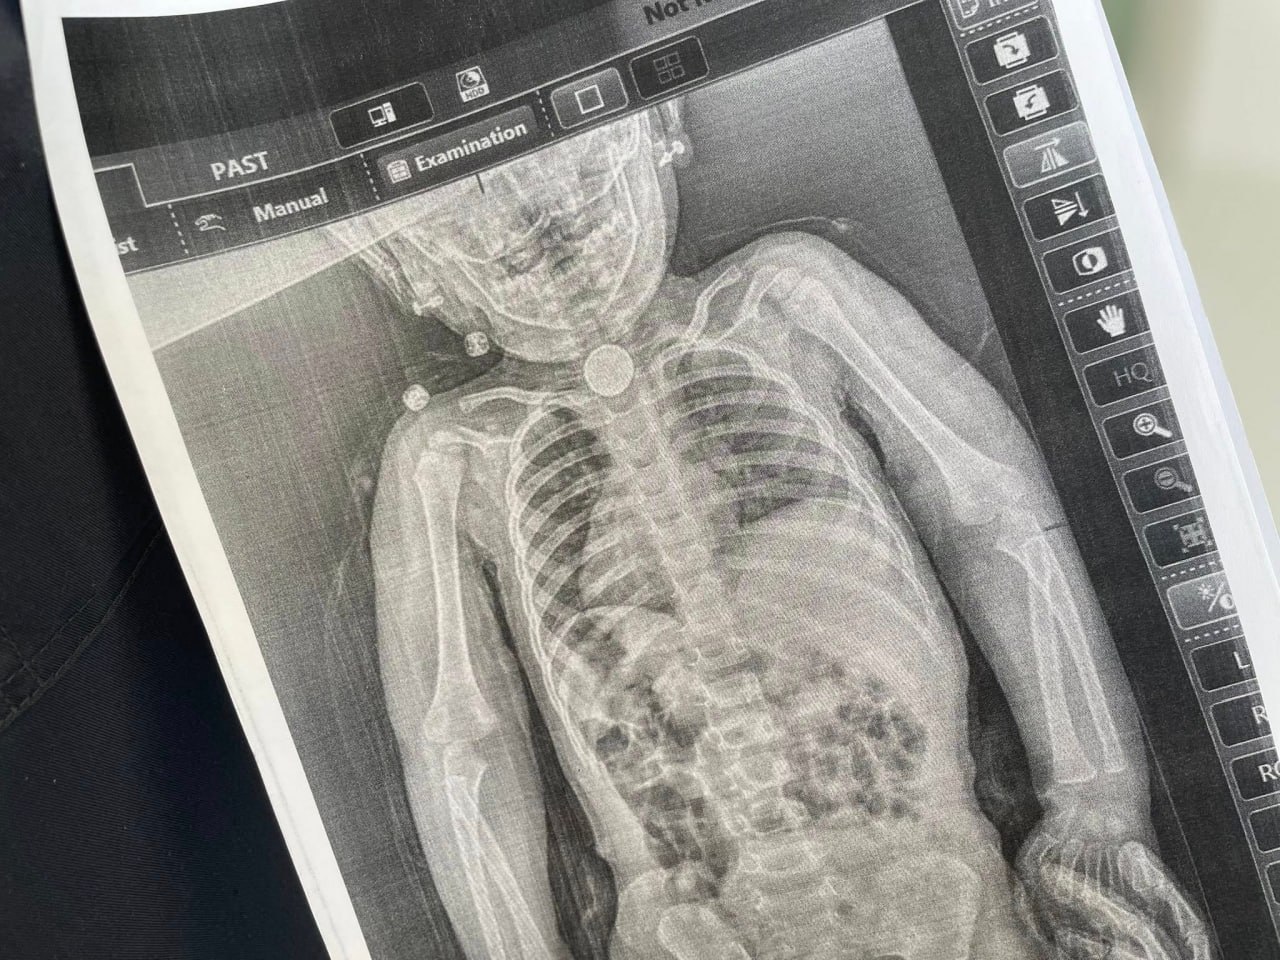

Лише після появи блювання, кашлю та свистячого дихання батьки наполягли на додатковому обстеженні. Рентген показав стороннє тіло у стравоході.

Під час ендоскопії лікарі виявили круглу літієву батарейку діаметром 2,5 см, яка щільно застрягла у стравоході та вже спричинила серйозне ушкодження тканин.